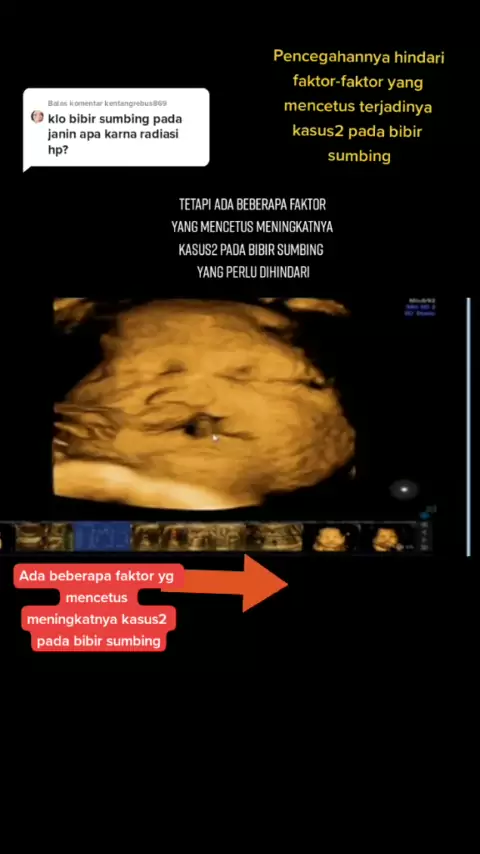

Balas @kentangrebus869 Coba di ingat syg waktu sebelum hamil dulu mgkin ada disalah satu yang sy sebut#edulive #educationmotivation